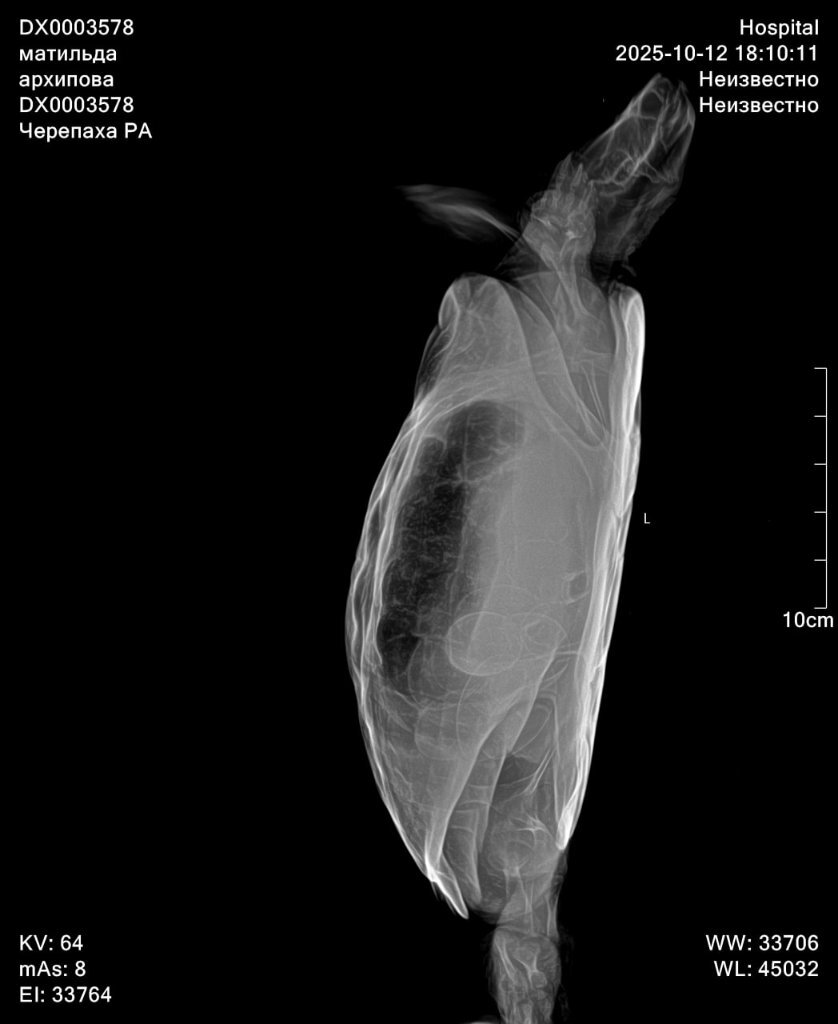

Здраствуйте, сегодня обратилась в другую клинику, прогноз не благоприятный, есть признаки почечной недостаточность, есть переизбыток бактерий в кале, есть признаки стоматита в полости рта. Все это очень и очень плохо. Сделали рентген по направлению, к сожалению описание рентгена рентгенологи сделать не могут, без дополнительной платы. Но завтра я уже записана со снимками на повторный приём. Моя огромная ошибка что ограничилась визитами к одному доктору, и потеряла очень много времени. Тк изначально состояние более стабильное хотябы визуально. Завтра получим назначения от главного врача специалиста по экзотам. Покажу им новые снимки. По фото вроде насчитала тоже количество яиц. Но они значительно сместились, вероятно из-за не к месту сделанного окситоцина